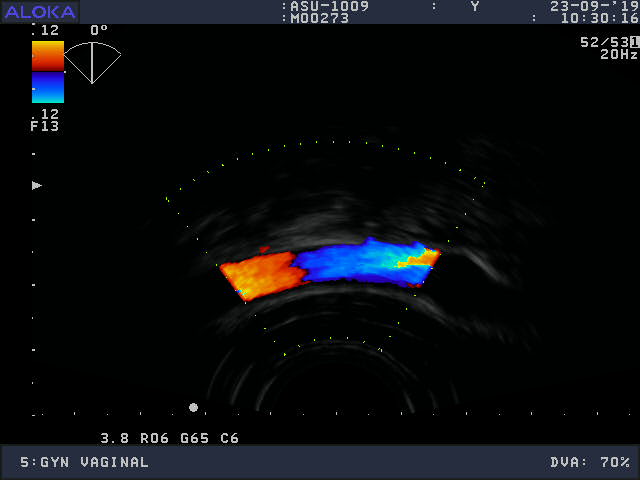

Volume Obstetric and Gynecology

Frequency Range: 9 – 3 MHz

Aloka ASU-1003 3D/4D Vaginal – ProSound for Volume Obstetric and Gynecology

| Type of examination 3D/4D | |